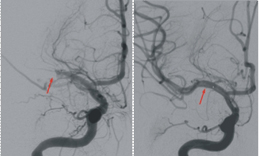

左圖紅色箭頭指出患者右中大腦動脈阻塞經過溶栓後, 右圖紅色箭頭顯示右中大腦動脈重新恢復通暢,術後患者運動功能恢復良好,無中風再發的情況。